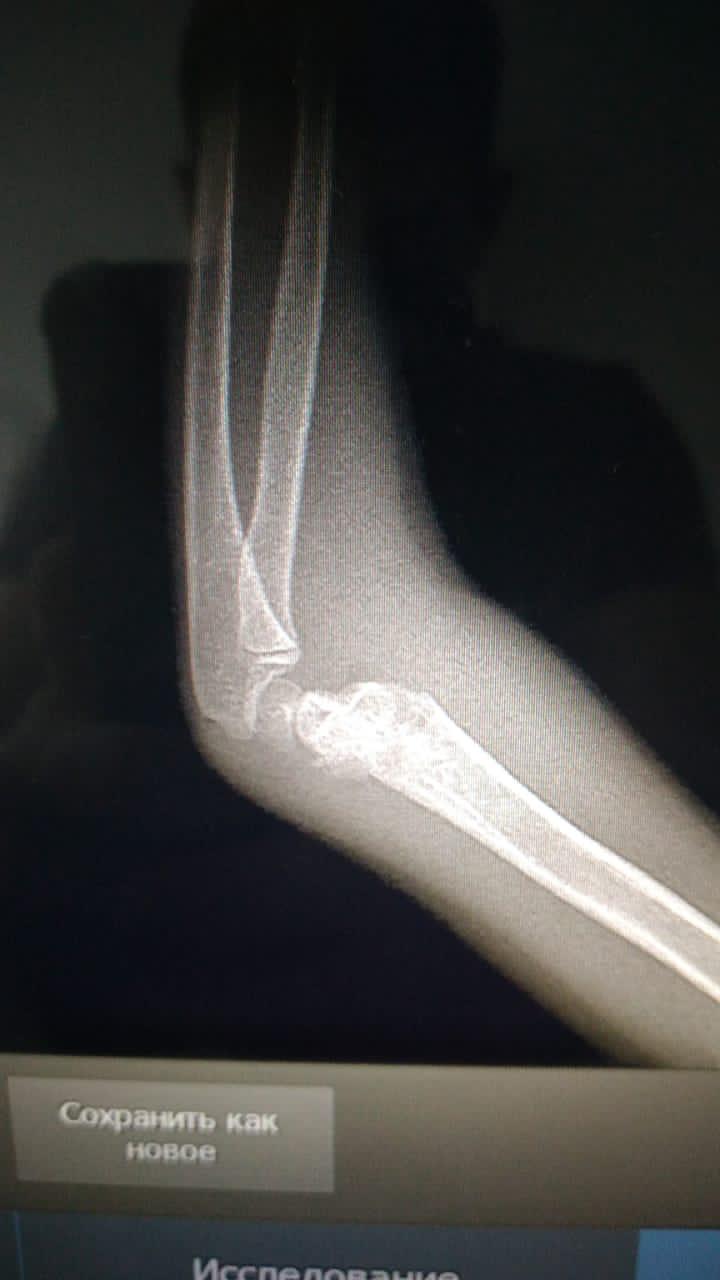

02.06.2021 жылы Жалағаш аудандық ауруханасына Ербол Аяна Ғалымжанқызы 2015ж.т. жедел хирургия бөліміне түсті. Науқасқа жедел түрде бөлім меңгерушісі М.Оспанов пен травматолог дәрігері Ж.Сыдықовтың қатысуымен "Электронды рентген аппараты бақылауымен жабық орнына келтіру, спица арқылы бекіту отасы" жасалды. Ота жасалған науқастың түскен кездегі диагнозы: Сол жақ иық сүйегі айдаршығының жабық ығысқан сызығы. Науқастың қазіргі отадан жағдайы қанағаттанарлық, шағымы жоқ.